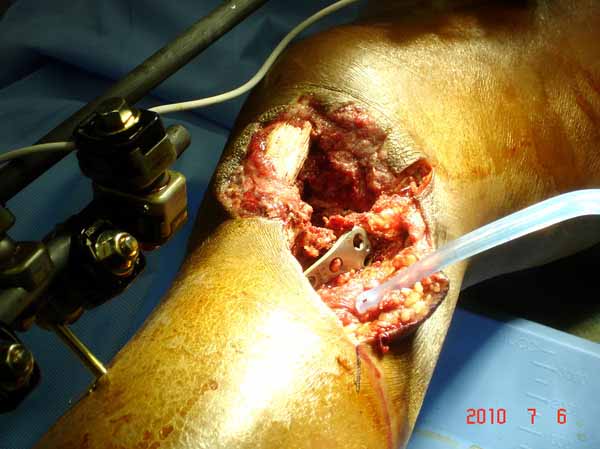

Больная Л., 23 года. Из анамнеза:со слов больной в 2006 г. появились боли правой н/конечности, обратилась поместу жительства к хирургу, было выполнена МРТ поясничного отдела позвоночника,назначено физиолечение. Через 2 месяца боли прекратились, через 4 месяца рецидив болевого синдрома. С 2006 – 2010 проводилось консервативное лечение по поводу остеохондроза поясничного отдела позвоночника. В октябре 2010 г. боли усилились. Выполнены Ro и КТ правого тазобедренного сустава, выявлен очаг патологической перестройки. Была направлена на консультацию в УНИИТО. В УНИИТО виюне 2011 г. поставлен дифференциальный диагноз между фибромой, солитарной костнойкистой и гигантоклеточной опухолью.

Клиника и течение заболевания похожи на однокамерную кисту. Больная молодая, желательно сохранить собственную головку. Надо спешить с операцией, иначе скоро произойдет перелом через тонкую стенку. Во время операции внутри будет пустота и небольшое количество жидкой крови.

Из всех перечисленных методов подходит вариант пластики аутокостью и усиление (арматура) шурупами. Основная задача сохранить интактную медиальную стенку и латеральный кортекс. Доступ передне-латеральный, но надо работать спереди шейки через небольшое окно в 10-15 мм. Фиксацию надо проводить между медиальной тонкой стенкой головки и латеральным кортексом. Каннюлированные шурупы 6.5 мм очень грубые и могут разрушить остаток стенки. Фиксировать надо кортикальными шурупами 3.5 мм, которые создадут мостик и арматуру в шейке. Провести по периметру шейки 4, и в центре пару шурупов. Во время операции и при манипуляции соблюдать осторожность, в любой момент может наступить стресс перелом. Заранее надо заказывать длинные шурупы!